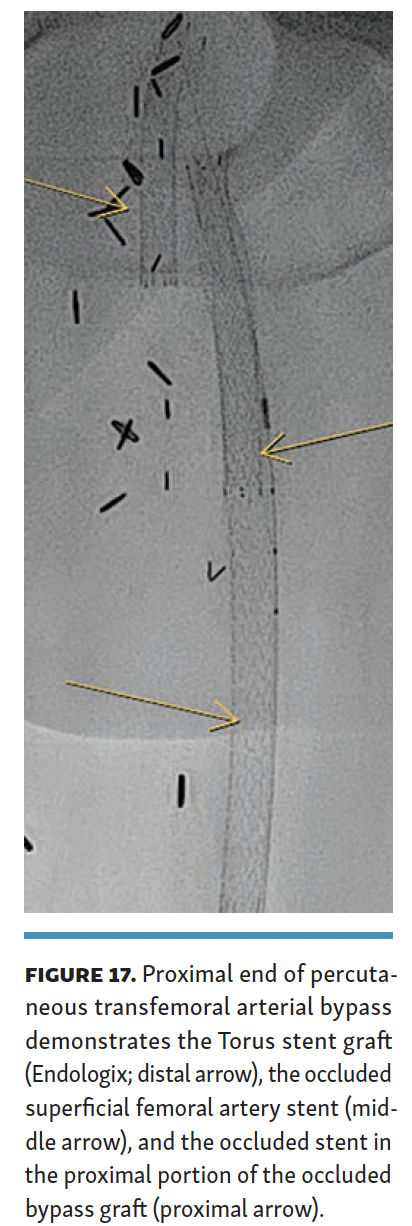

The arteriovenous connection was then ballooned, and the Endocross device was advanced into the femoral vein. Distal angiogram demonstrated multiple areas of occlusion in the distal SFA with the stent in the occluded vein bypass graft entering the proximal popliteal artery (Figure 11). Re-entry into the popliteal artery was obtained below this segment. Following dilation of the retry site (Figure 12), the Torus stent grafts were deployed distal to proximal. Completion angiogram after angioplasty of the stent graft demonstrated brisk flow proximally and into the popliteal artery (Figures 13 and 14). Venogram demonstrated unhindered flow through the femoral vein (Figure 15), and intravascular ultrasound imaging of the femoral vein demonstrated an adequate venous lumen next to the intravenous Torus stent graft (Figure 16). The patient was discharged the following day on 20 mg of rivaroxaban and 81 mg of aspirin once a day. Fluoroscopy of the proximal end demonstrated the Torus stent behind the prior SFA stent and the occluded stent in the proximal portion of the vein bypass graft (Figure 17). Procedural time was 139 minutes, fluoroscopy time 39 minutes, total contrast volume 100 mL, AK 332 mGy, and DAP 5550 µGym2.

Two different techniques were used to cross the occluded stents. The technique used was based on the ease of wire crossing, either through or behind the occluded stent. In neither technique, completion angiogram nor follow-up duplex imaging, demonstrated any flow compromise; however, the retro-technique had less proximal angulation of the torus stent graft on the completion angiogram (Figures 8A and 13). The retro-stent technique is more challenging due to the need to create a channel directed to the location of the femoral vein (posteromedial in most patients). If the channel created is located anterior or lateral to the occluded SFA stent, the Endocross would essentially have to cross 2 layers of nitinol stents to reach the femoral vein, which would create a greater risk of technical failure. Additionally, the Torus endograft would then have to traverse 2 layers of nitinol stents with increased risk for compression and stent fracture.